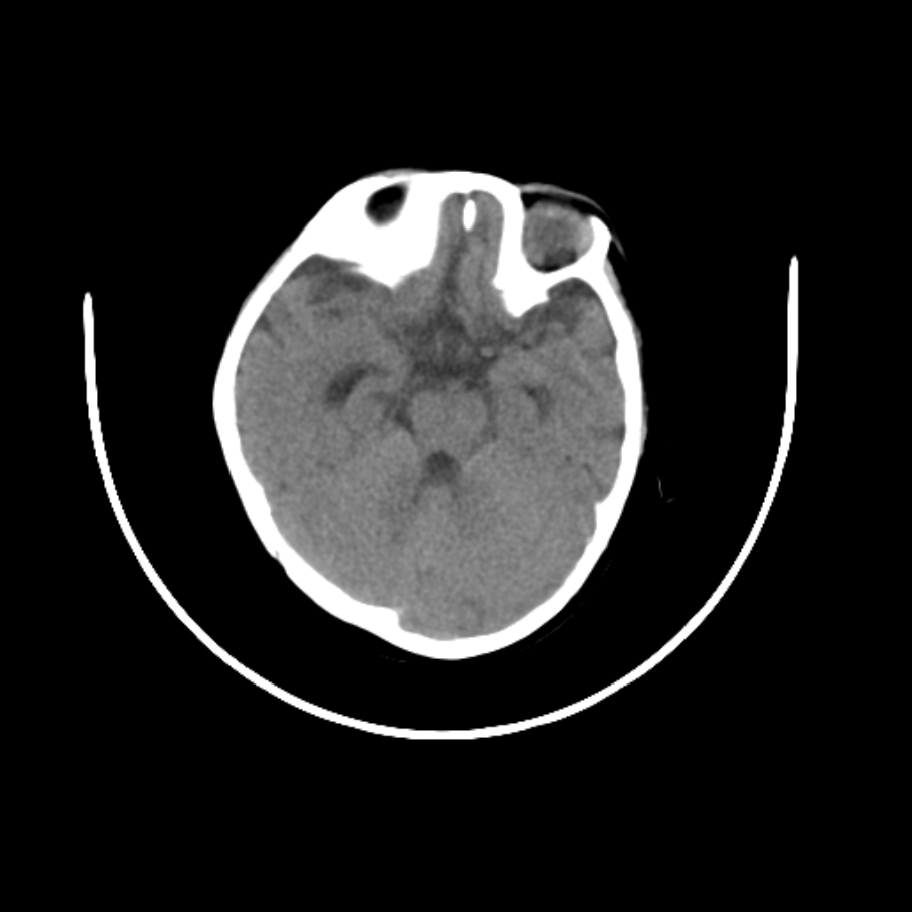

以下是引用随光逐影在2009-4-8 7:51:00的发言:[br]1)透明隔缺如(视-隔发育不良?)。2)右侧脑裂畸形。3)右侧幕上半球脑萎缩。